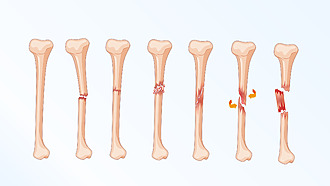

Types of fractures

Fractures are divided into several groups according to what the fracture site looks like. Where parts of the bone are displaced or whether the bone penetrates through the skin.

- Closed

The bone stays under the skin and does not come out of the wound. - Open fracture

The bone penetrates the skin. - Dislocated fracture

Parts of the bone may shift in some fractures – for example, sideways or lengthways. - Stess fracture

It occurs, for example, due to long-term or unilateral stress. Athletes are typical patients with a fatigue fracture.[8]

Fractures can have different fracture lines. The bone may fracture transversely, obliquely or in a spiral. A splinter fracture can also occur.[9]